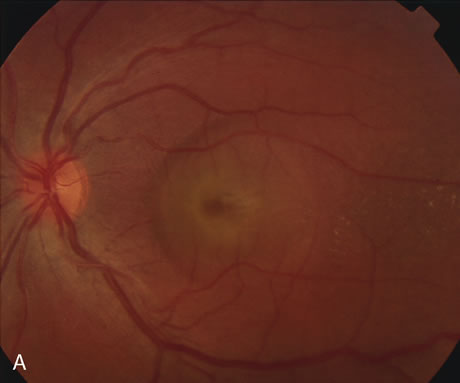

Central serous chorioretinopathy (CSC) is characterized by breakdown of the outer retinal barrier, with leakage of fluid through a defect in the retinal pigment epithelium into the subretinal space, resulting in a serous neurosensory detachment.78–205 The ophthalmologist can usually diagnose CSC based on the clinical examination and demographic information.93–95 Most patients with CSC are middle-aged men74 who often have type A personalities.75, 96–104 CSC has also been associated to the use of corticosteroids,105–118 pregnancy,119–126 increased adrenaline level and stress,127–132 hemodialysis,133,134 collagen vascular diseases,135–147 and hypertension.148–157 CSC typically presents as a large serous detachment in the posterior pole without an obvious source of the subretinal fluid.76 However, because a small CNV cannot be ruled out, FA is usually done to confirm the diagnosis. Characteristically, there is a small RPE defect, which hyperfluoresces early, and then there is slow filling of the overlying neurosensory detachment, which may have a classic “smokestack” (Fig. 21) or “ink blot” (Fig. 22) appearance.158–161 Occasionally, FA demonstrates multiple sites of leakage (Figs. 23, 24, and 25). FA sometimes fails to distinguish CSC from CNV readily because fibrinous subretinal precipitates can cause slow filling of the RPE detachment, which is suggestive of CNV (Fig. 26). Sometimes peripapillary PCV can cause a neurosensory macular detachment masquerading as CSC (Fig. 27).77

Fig. 21. Central serous chorioretinopathy. A. There is a central retinal pigment epithelium (RPE) detachment with linear RPE hyperplasia in a “hot-cross bun” configuration, indicating that the RPE detachment is chronic. B. This late fluorescein photograph illustrates leakage of fluorescein into the neurosensory detachment, with a classic “smokestack” formation.